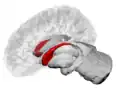

![]() Caudate nucleus (in red) shown within the brain | |